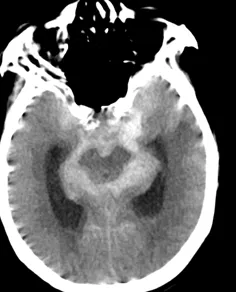

生死关头,急诊团队立即启动紧急抢救预案,并加急安排急诊头颅CT检查。检查结果确诊为蛛网膜下腔出血,神经外科专家紧急会诊后,进一步明确病因是颅内动脉瘤破裂,且患者病情已达Hunt-Hess V级——这是颅内动脉瘤破裂中死亡率、病残率很高的重症级别。

▲术前头颅CT